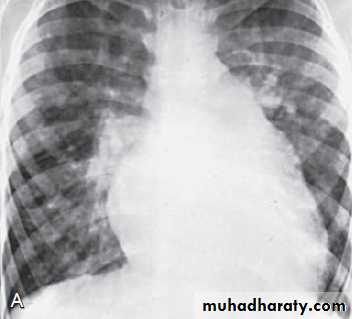

CXR in patient with VSD shows cardiomegaly & pulmonary overcirculation